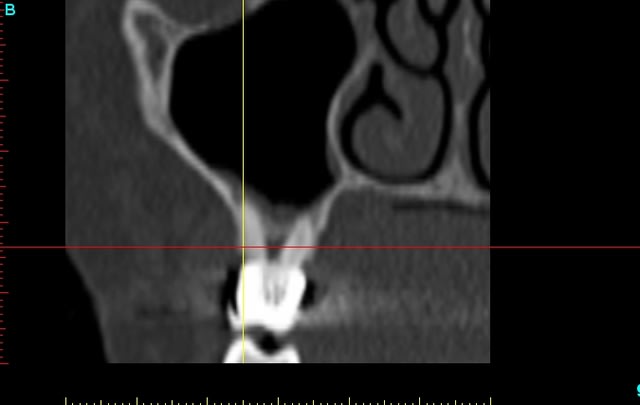

demain je chasse, mais lundi, je vais prendre le temps de modeliser le scan, pour controler les apex

Tu as l'air de vouloir fermer les yeux sur l'origine de la douleur en devitalisant "par principe de sécurité" les 2 dents et à coté de cela tu modélises les apex... Par cet examen tu cherches à objectiver quoi exactement?

je recois un scan , je regarde tout simplement si pbs au niveau des apex!Il n'y a rien de particulier

je regardais aussi si les dents etaient saines avant le bridge